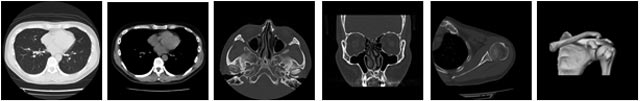

CT検査について

当院のCT装置はCanon社製Aquilion Lightningを使用しています。このCT装置は、16列のタイプで人体の断面像を得ることが出来ます。画像を得るために使用しているエネルギーは放射線で、検査の際には放射線被曝を伴います。しかし、診断に必要な画質を保ち、なおかつ必要最低限の放射線量を使用しているため、安心して検査を受けて頂いています。